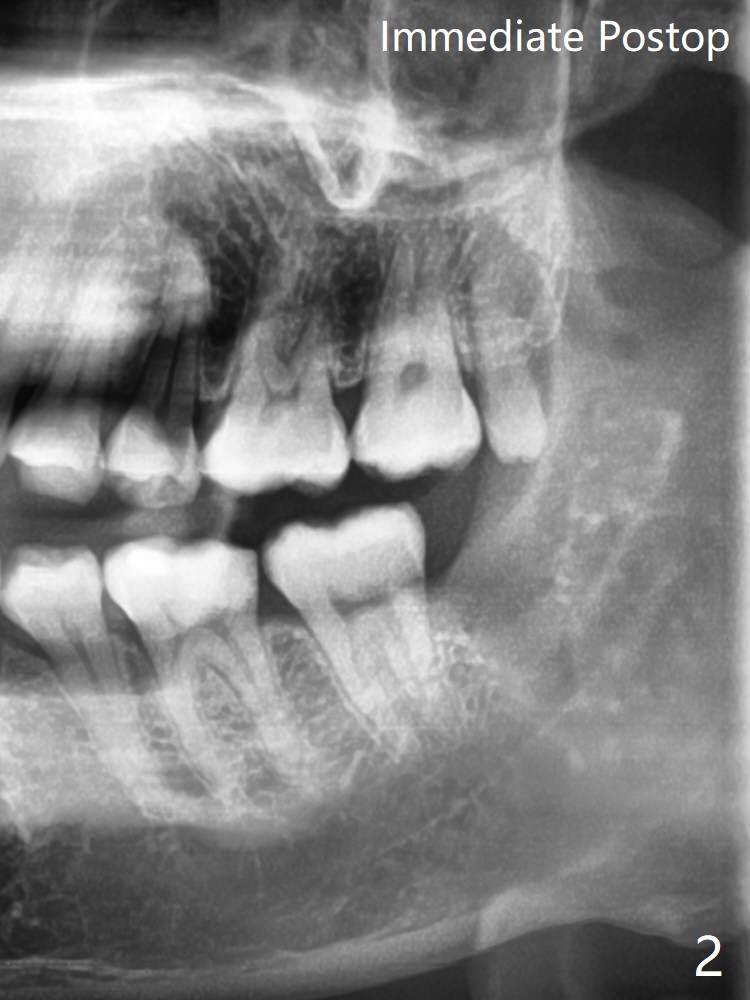

#17 Traumatized by #16

A 30-year-old man complains of chewing pain at #17. The distal gingiva seems to have been traumatized (adhesion) by the opposing 3rd molar (Fig.1 arrow). The tooth is out following sectioning twice with the socket inserted with Osteogen plug (Fig.2). Return to Plug Xin Wei, DDS, PhD, MS 1st edition 05/19/2021, last revision 05/20/2021